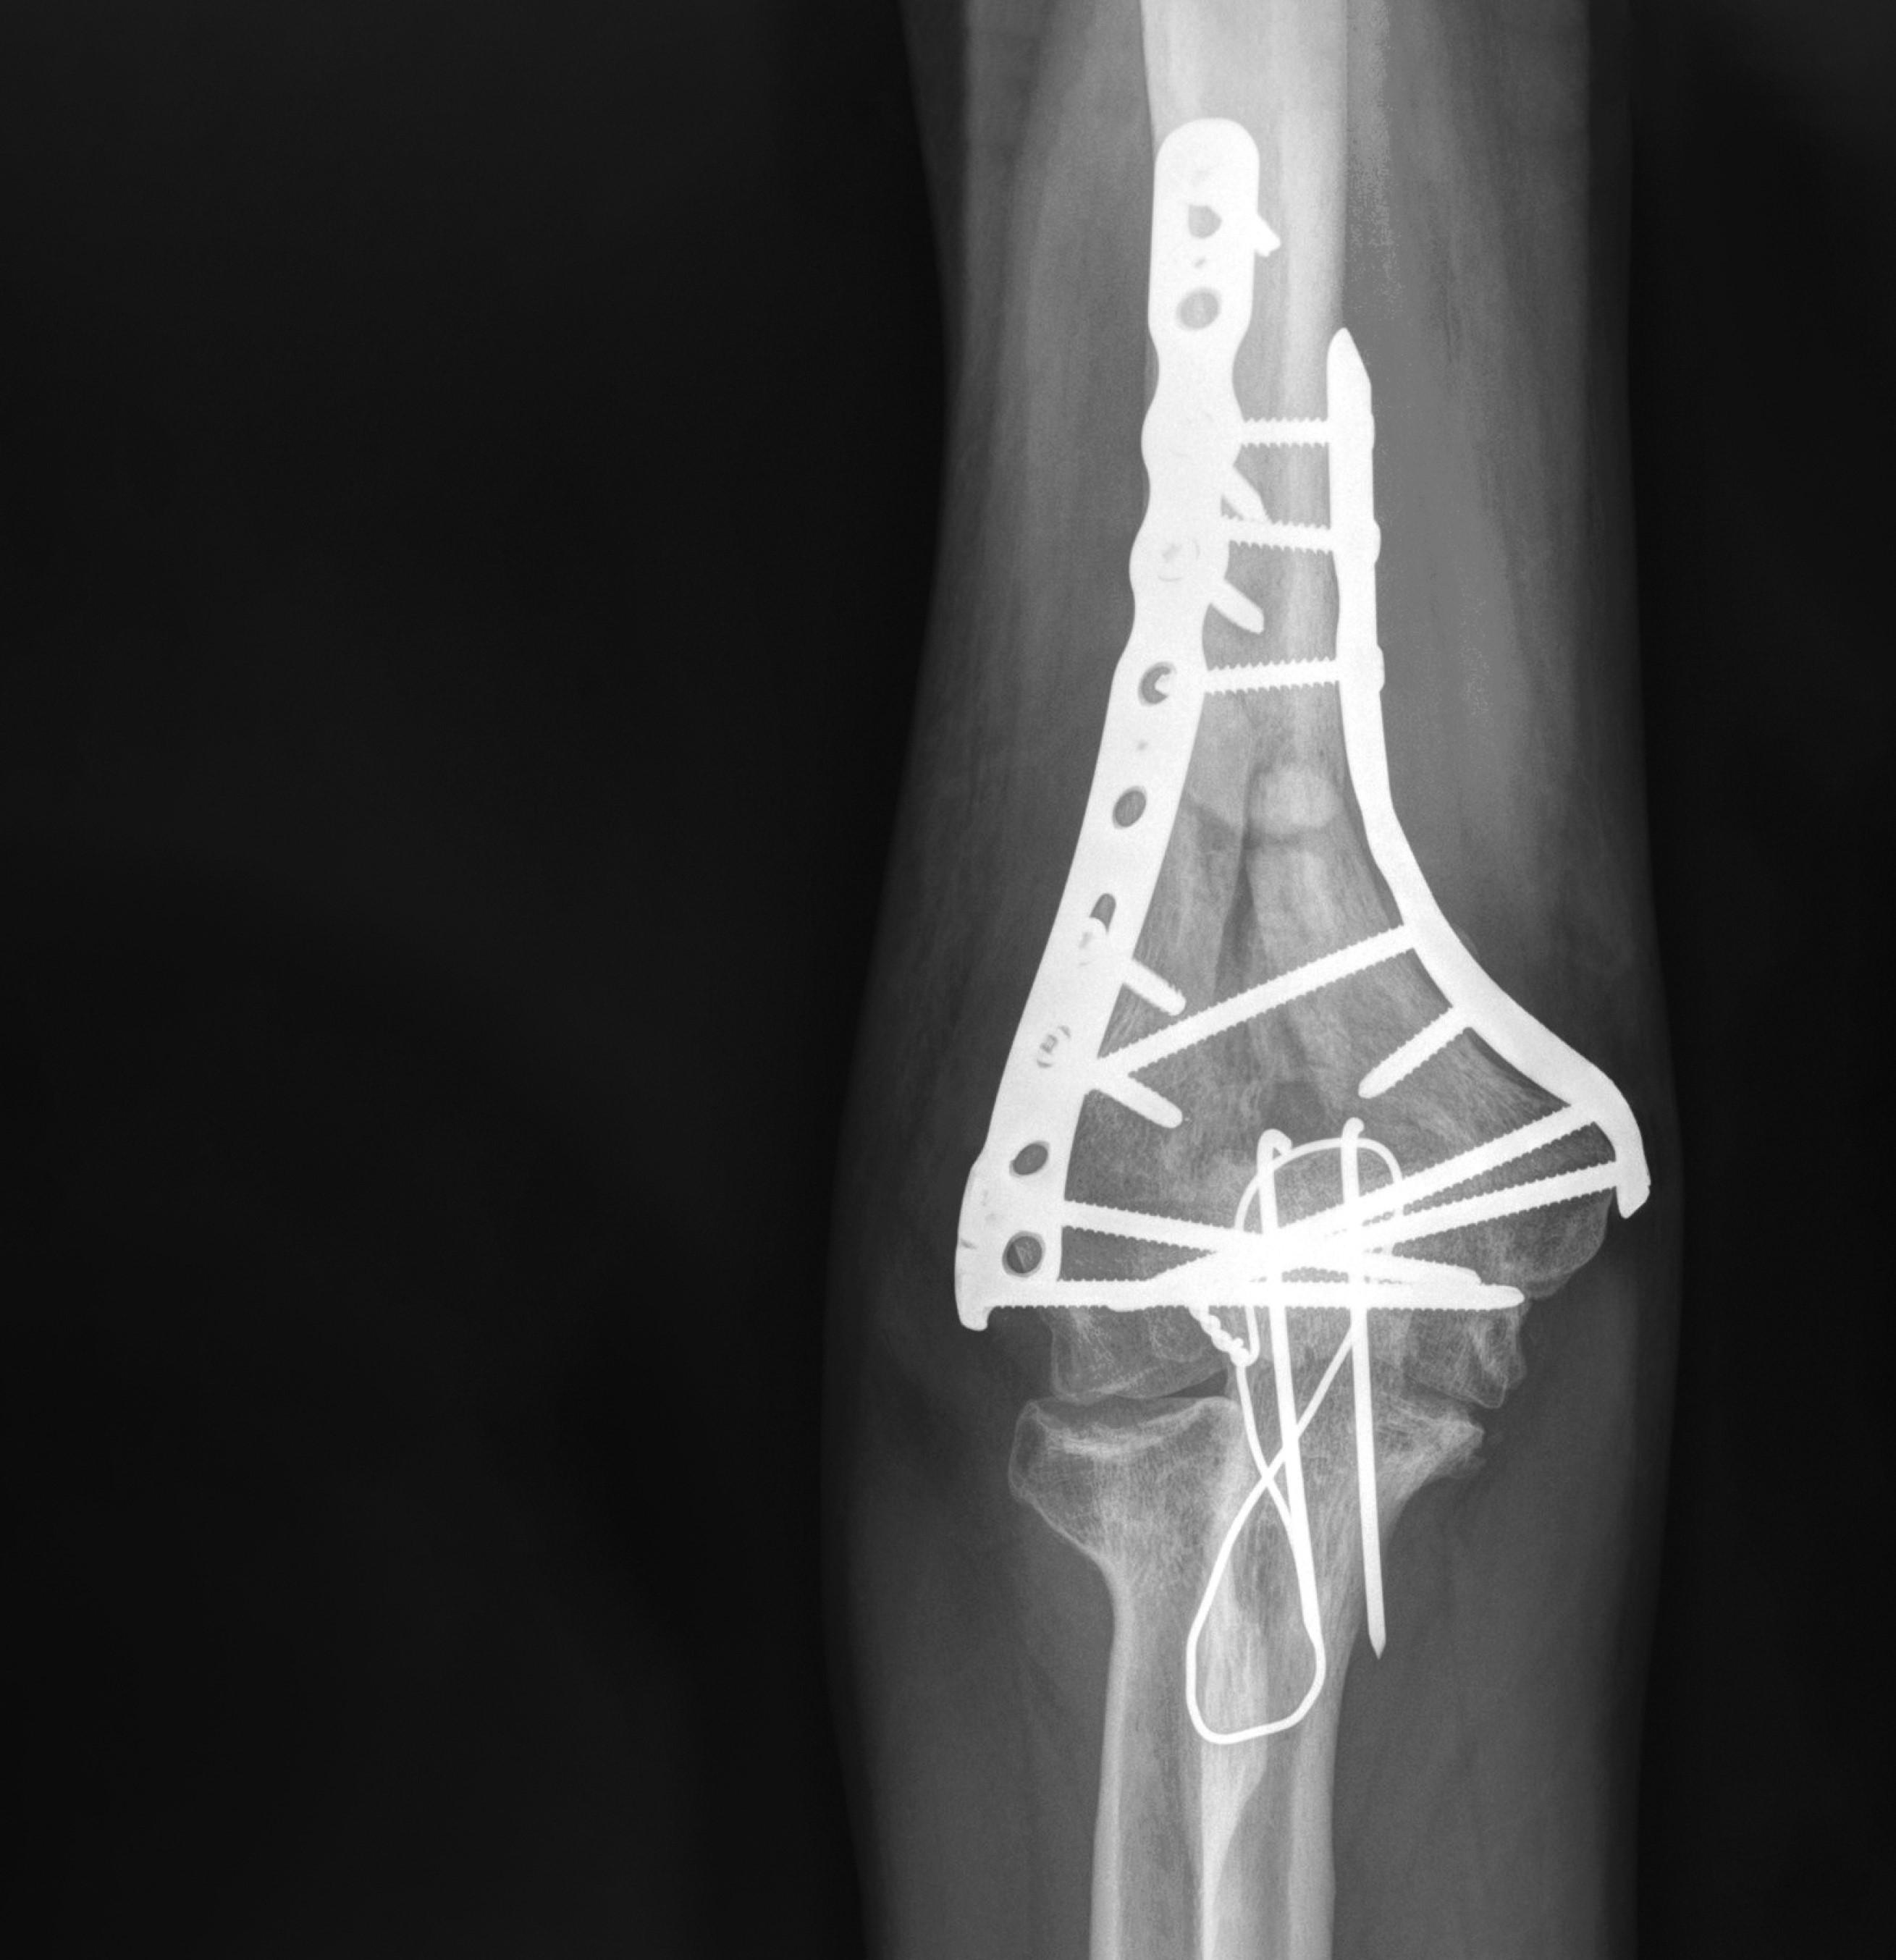

LORRAINE CLINICAL CASE: MULTIFRAGMENTARY INTRA-ARTICULAR FRACTURE OF THE DISTAL HUMERUS

We present a case of a 46-year-old male patient who presented to the emergency room after a fall from a roof at work.